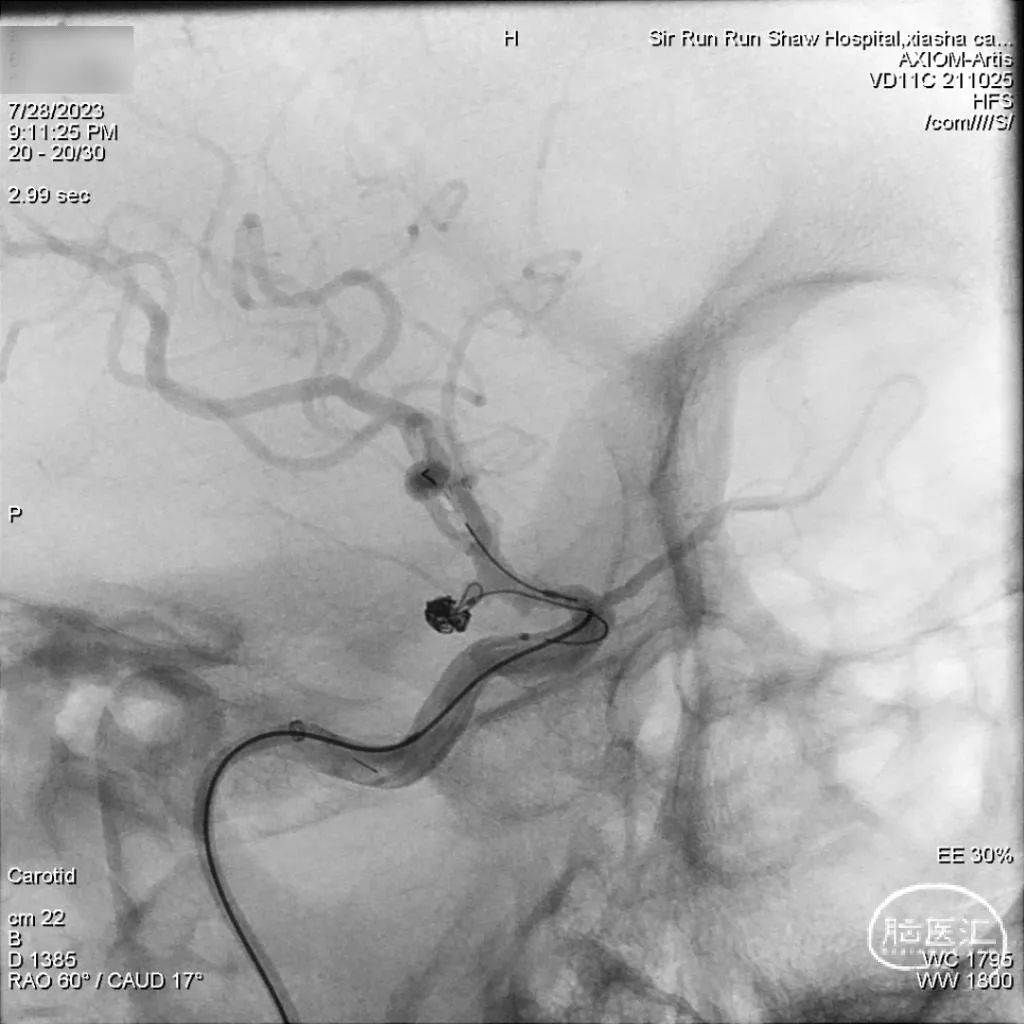

手术过程

弹簧圈微导管Echelon 10到位。

术后桡动脉压迫器压迫穿刺口,术后CT未见出血、梗死。患者术后即清醒拔管,无新发阳性症状。术后第二天予口服双抗重叠6小时后停用替罗非班,术后患者未出现血栓事件。

经桡动脉入路建立通路,我们选择同轴的方式,相较交换,更加快捷、安全。使用Sim 2形状的MPA勾选目标血管,Tethys®中间导引导管实现高到位。因市面缺少125cm的Sim 2导管,我们使用125cm 5F的多功能造影管手动塑形,也可达到Sim 2反向勾选颈总动脉的效果。因Tethys®中间导引导管近端抗打折的属性,锁骨下动脉至颈总动脉的转折处,不易弯折而损失内腔,管腔通畅有保障。因Tethys®中间导引导管近端有良好的支撑力,故弯折处可承受较高的后座力,系统不易因上方张力过高而掉入主动脉弓或升主动脉,操作过程无后顾之忧。因Tethys®中间导引导管头端柔软,实现了通路高到位,为微导管、导丝及后续的操作提供稳定的平台。

患者动脉瘤形态不规则,远近2处囊泡,微导管塑形理想,先超入远端囊内,由远至近依次填塞,过程安全,也有机会达到致密栓塞的效果。考虑到动脉瘤大概率未出血,且宽颈,支架辅助栓塞可提高一期治愈的机率,遂行支架覆盖瘤颈,效果理想。因此例患者为近期急诊手术,住院期间头痛、眼球胀痛已明显缓解,团队也会关注后期复查的情况,期待有好的随访结果。